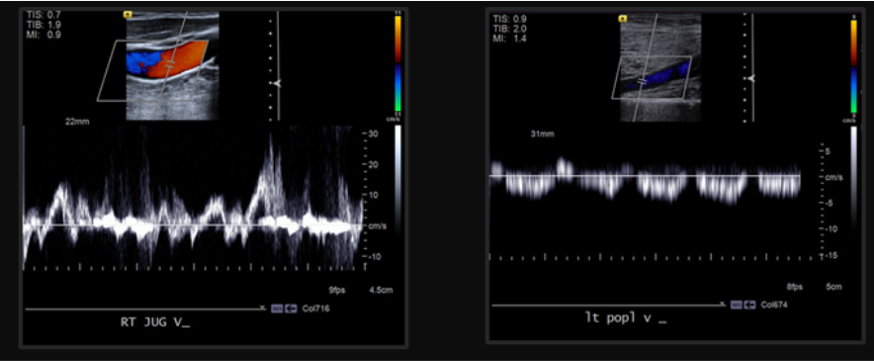

right groin US image with color doppler. What intervention did the pt likely have, diagnosis, and what is the treatment?

femoral artery pseudoaneurysm with classic “yin-yang” sign indicated to and fro flow into and out fo the pseudoaneurysm sac.

likely right femoral arterial access recently (like heart cath)

treatment = ultrasound guided thrombin injection. GOAL: introduce thrombogenic material under sonographic visualization to eleimate visible flow within the pseudoaneurysm sac